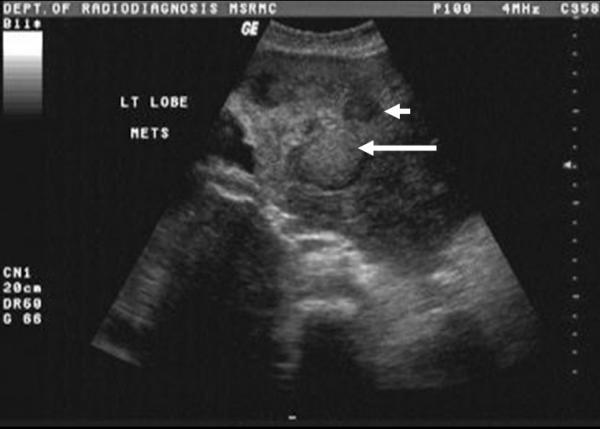

We report a 60 year old female patient who presented with adenoid cystic carcinoma of the parotid gland. She underwent a total conservative parotidectomy followed by adjuvant radiotherapy. While on follow up, patient developed multiple liver metastases which manifested three years later. Patient lived for another two years before she died of her disease.

我们报告一名60岁女性患者,患有腮腺腺样囊性癌。她接受了全腮腺保守切除术,随后进行辅助放疗。在随访期间,患者出现多处肝转移,三年后表现出来。患者又存活了两年,最终死于该疾病。